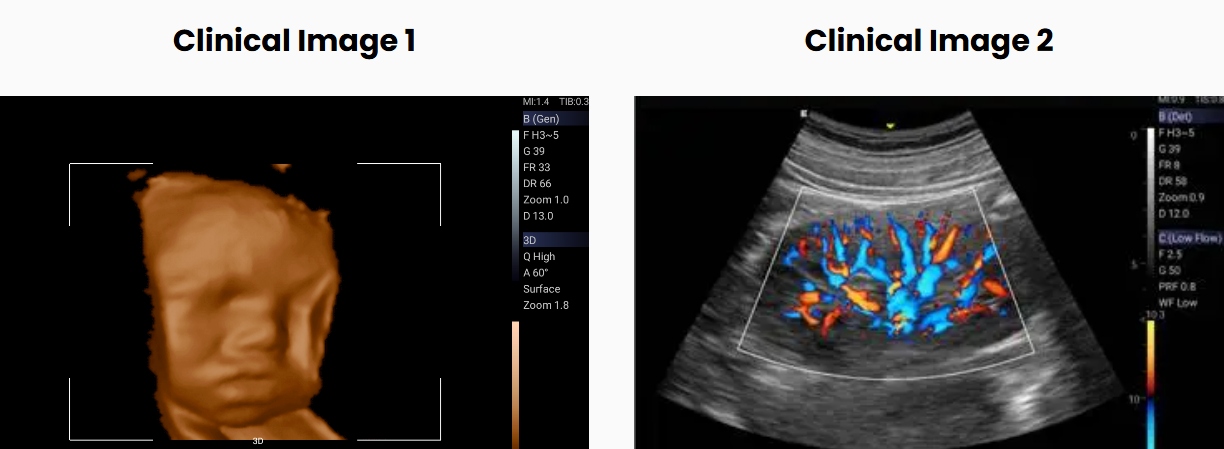

Complete scanning mode package including 3D/4D

Integrated with compact appearance, cutting-edge technology and intelligent workflow, Acclarix LX3 is to provide more valuable innovation.

Compacted with innovative Edan TAI technology and multiple imaging processing technologies, Acclarix LX3 could perfectly display ultrasound image in different modes, assisting sonographer to make more precise diagnosis.